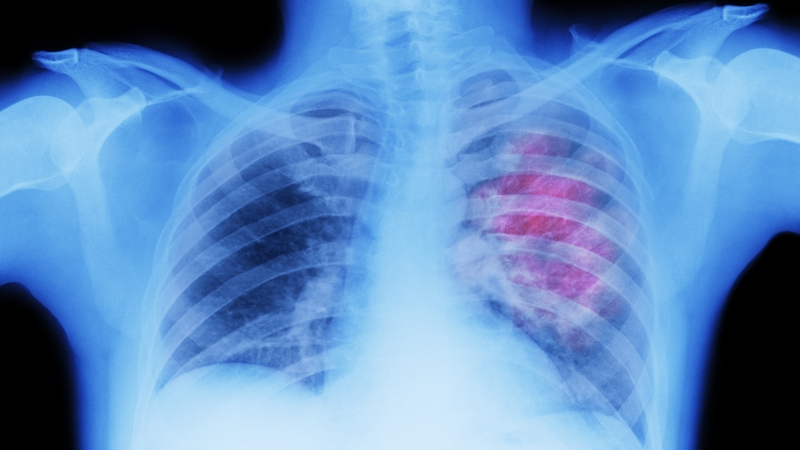

While doctors and nurses fought to contain deaths due to Covid-19, regular screening and care in other diseases including cancer, the number one cause of death prior to the pandemic, was compromised. The pandemic had a disastrous impact on cancer patients and those at risk of developing cancer. Many didn’t attend screening for fear of contracting Covid-19. In addition to no shows, many surgeries, biopsies and screening were postponed in response to lockdowns and the much needed response to Covid-19.

As people now begin to return, screening services and cancer care are at risk of being overwhelmed with demand. It is a race against time to identify those missed cancer diagnoses. Caught early, most cancers are treatable.

The Europe-wide numbers are startling: we estimate that 100 million people missed cancer screening tests, and as many as one million Europeans may be walking around with an undiagnosed cancer. In the UK, we found that seven out of every ten UK citizens with suspicion of cancer weren’t being evaluated by cancer diagnostic services, while four out of ten UK cancer patients were either missing chemotherapy appointments or not receiving chemotherapy at the right time. The Irish data, while incomplete, also highlights the significant impact of the pandemic.